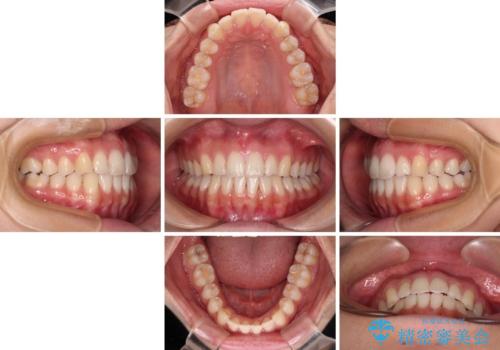

前歯の重なりをインビザライン・モデレートで矯正治療

- 上下前歯の重なりを気にして来院された患者様です。

安価なインビザラインパッケージを用いての治療を希望されており、デコボコの程度が中等度であったため、インビザライン・モデレートを用いて矯正治療を行うこととしました。

インビザライン・モデレートは、製作できるアライナーの枚数に制限があるため、移動可能な量に限りがあるものの、インビザライン・ライトよりも枚数が多いため、幅広い症例に対応可能です。